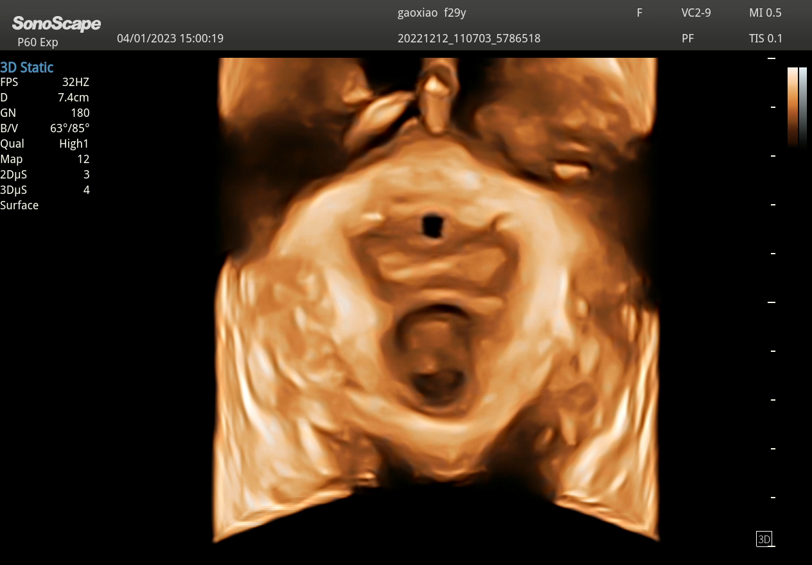

SonoScape S50 Elite – учитывая ключевые потребности и задачи врачей УЗД, S50 ELITE переопределяет спектр ухода за пациентами в своем сегменте, особенно для акушерско-гинекологических применений. Чтобы создать легкий путь к захватывающему ультразвуковому исследованию, S50 ELITE обеспечивает деликатное сочетание выдающейся клинической точности, повышенной производительности и продуманного рабочего процесса. Мы верим в то, что сможем предоставить клиницистам возможность быстрой и надежной диагностики, и S50 ELITE – это решение.

- 4D – режим трехмерной реконструкции в реальном времени

- Расчеты для акушерства, гинекологии, ангиологии, урологии, ортопедии, поверхностных, абдоминальных органов, кардиологии, головного мозга и сердца плода (в том числе STIC), вывода кривых роста плода, автоматический анализ толщины комплекса интима-медиа